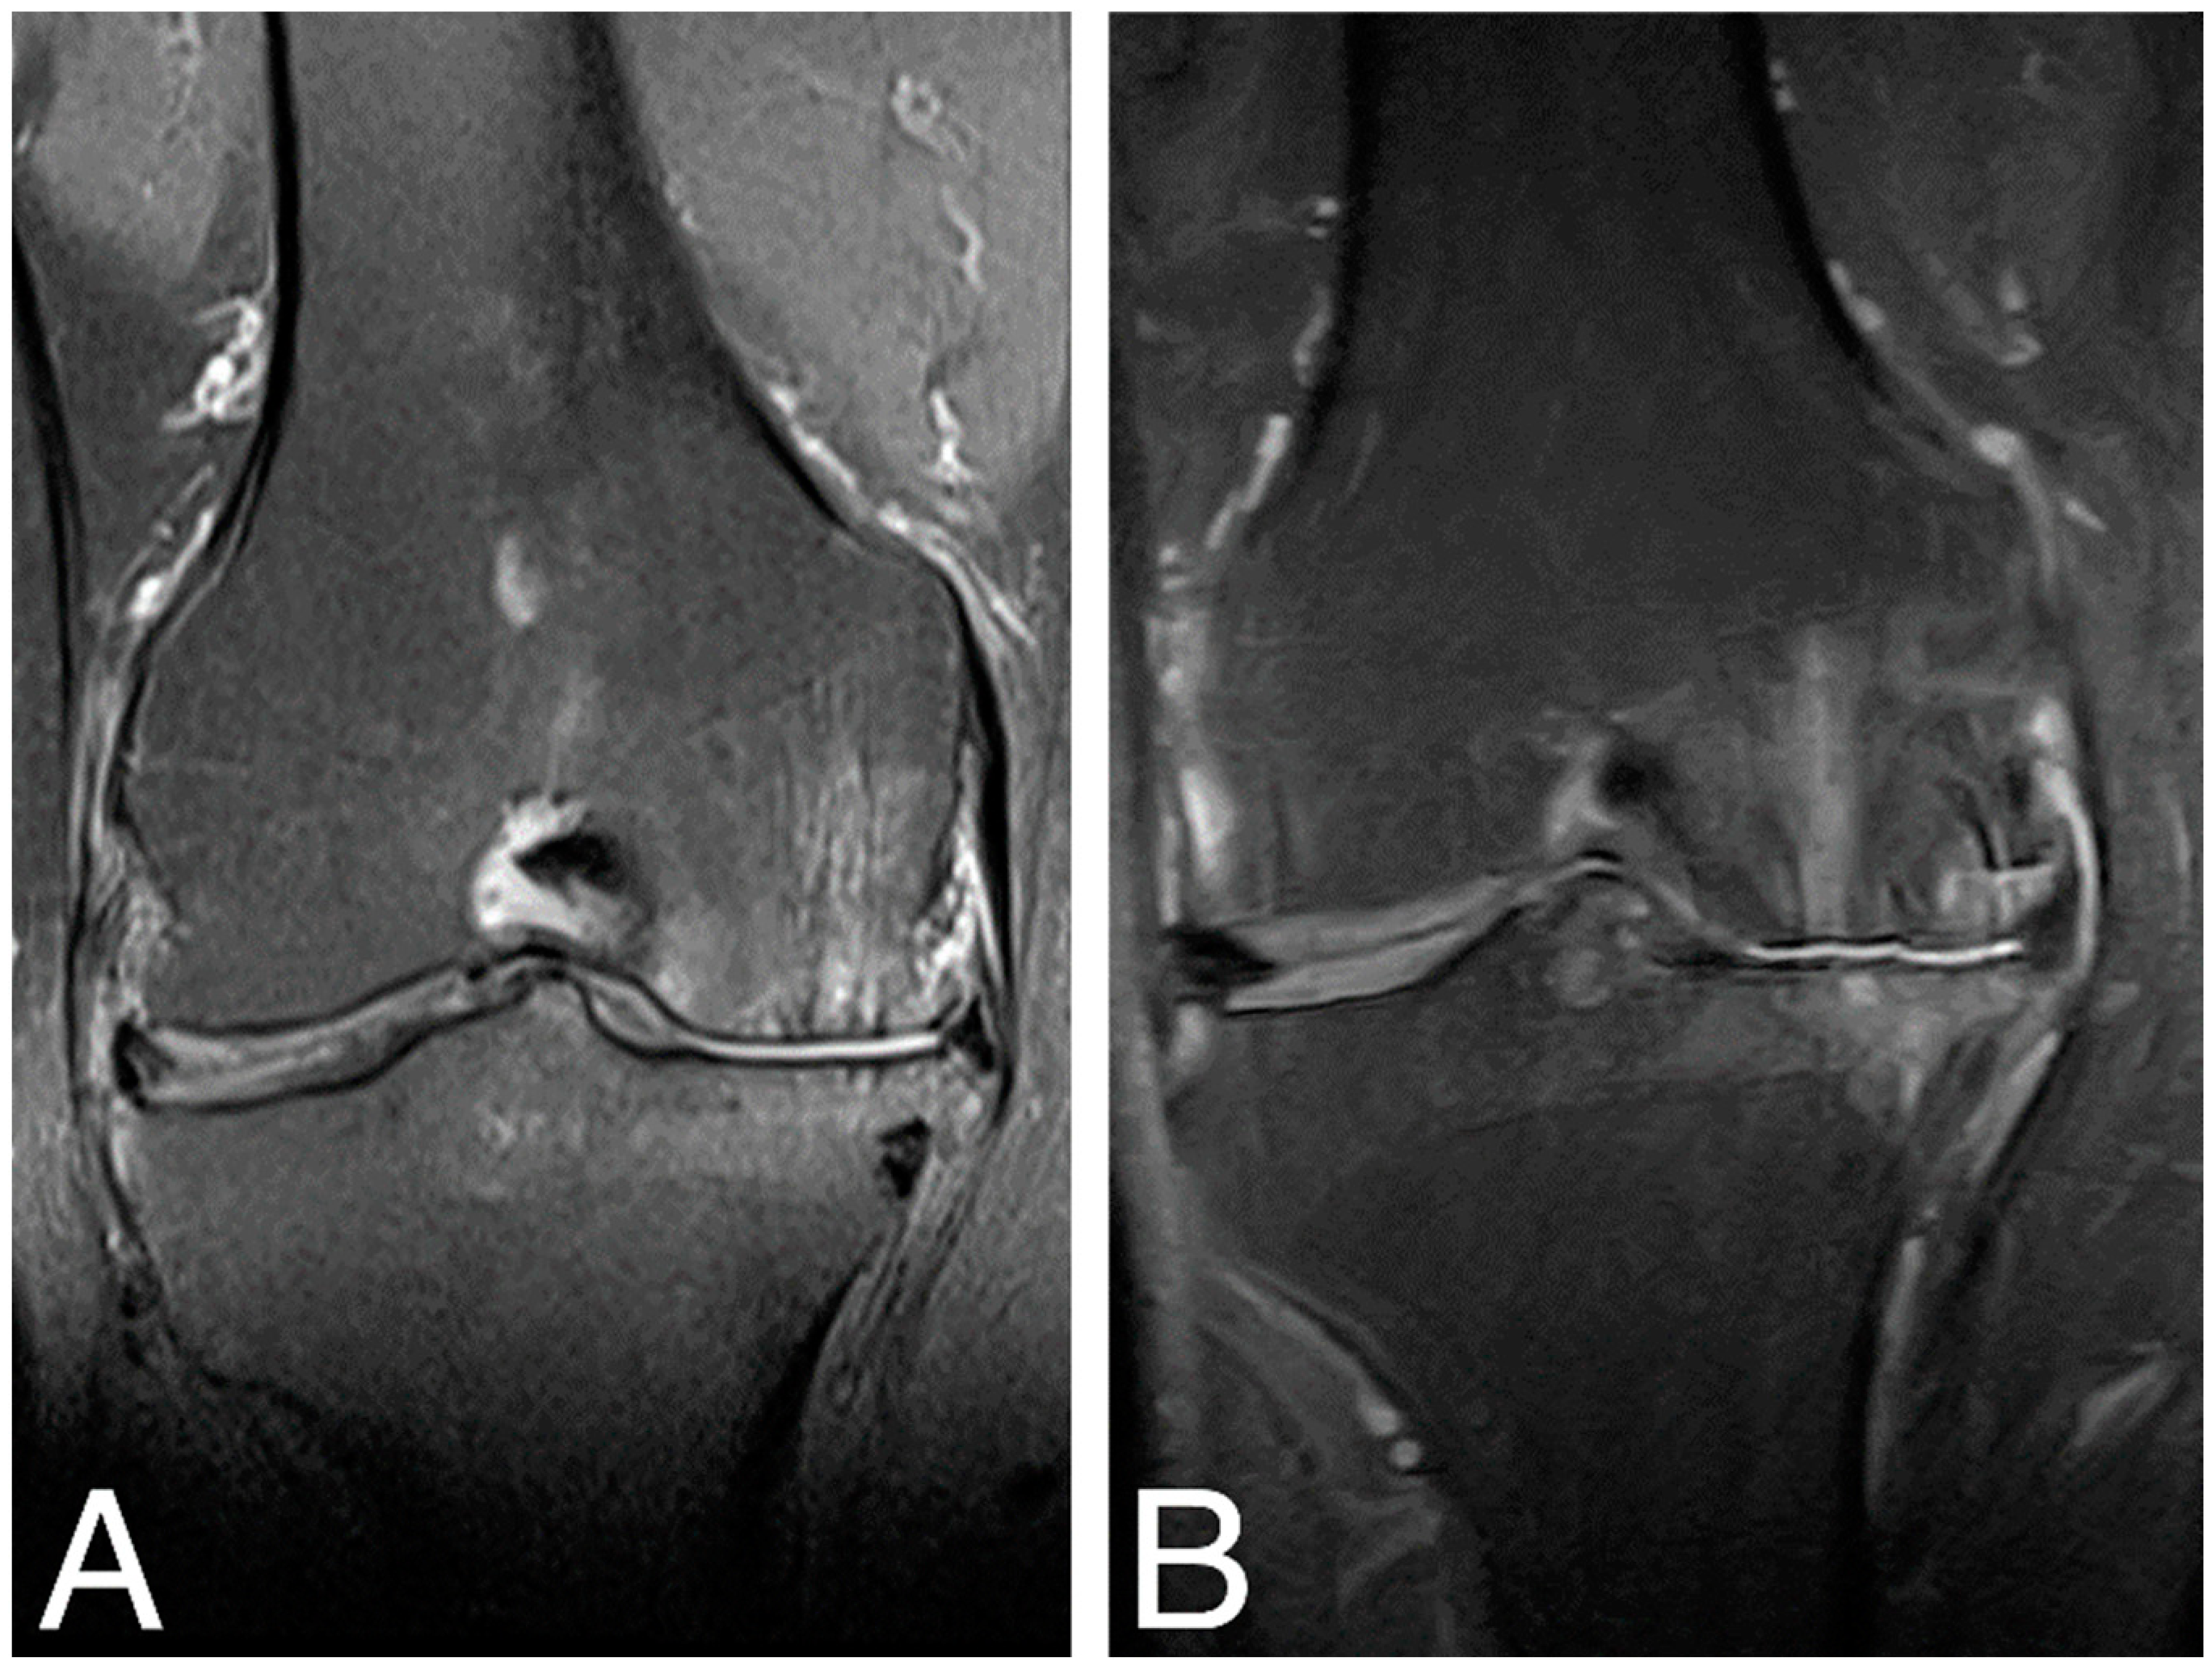

MRI examination of the treated knee joints was performed at baseline, 18 months [18], and 84 months time points. Results were ambiguous, showing both an increase in subchondral bone edema and consolidation of the articular cartilaginous surface. Figure 4. shows MRI findings of the same patient as in Figure 3.

Figure 4.

MRI images of the right knee, T2 sequence, and mid-joint frontal plane. (A) baseline (MOCART score 0.4); (B) 84 months time point (MOCART score 0.35).

Knee articular cartilage structure and integrity were evaluated using the MOCART score (range from 0–1) (Figure 5), where a higher score indicates better cartilage structure. The average MOCART score at 84 months was 0.49 ± 0.119, which is significantly worse than 0.63 ± 0.172 observed at 18 months (Wilcoxon signed-rank test, Z = −2.028370, p = 0.042522), but still significantly better than the baseline value (0.42 ± 0.072, Z = −1.991741, p = 0.046399). In two cases, we observed clear cartilage deterioration with scores at 84 mo decreased back to baseline values (0.3 and 0.4). Conversely, in another two cases, the 84 months score was either equal to (0.65) or even higher (0.45) than the 18 months score. The four other cases showed some degree of MOCART score lowering between 18 months and 84 months but still above baseline values (Supplementary Material, Table S2).